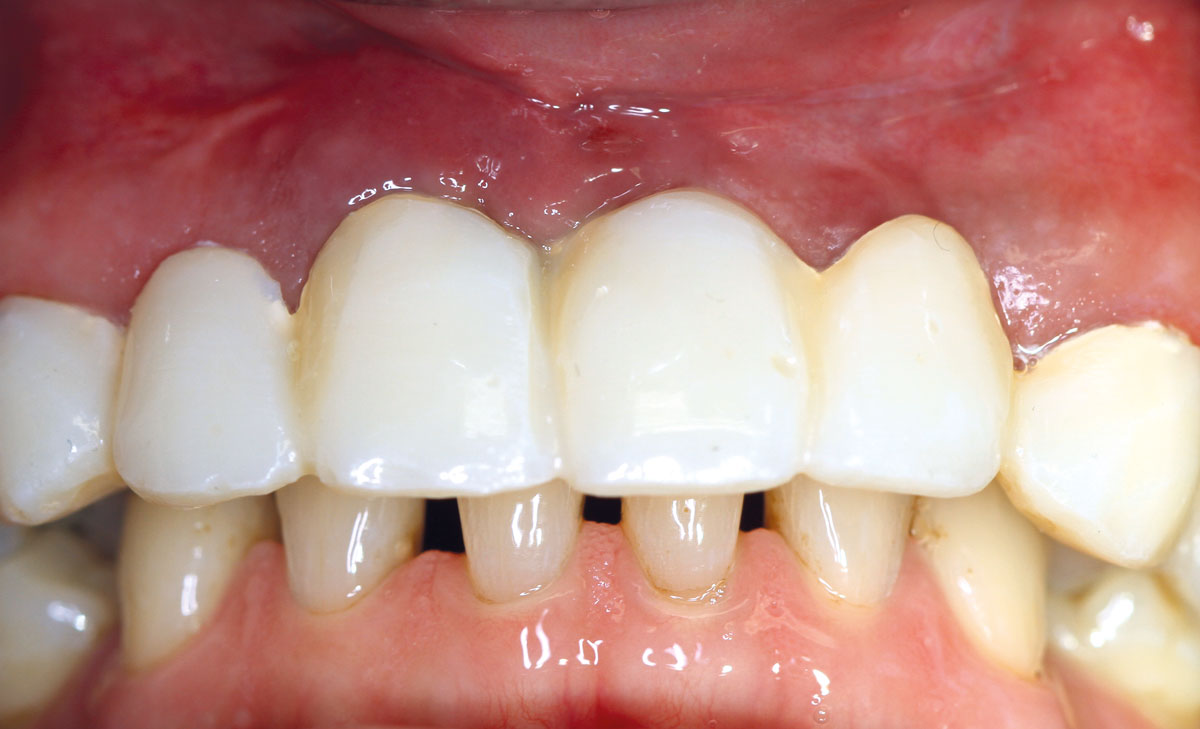

17/17 - Temporary provisionRestoration of all four incisors with maxgraft® bonebuilder - Dr. Dr. Dr. O. Blume